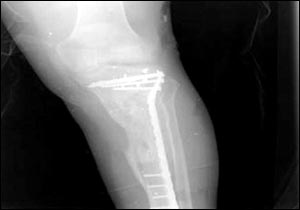

烏代傷腿的X光照片

7月24日,美國國防部通過由美國資助的伊拉克電視臺、兩家阿拉伯衛(wèi)星電視臺以及美國本土的CNN(有線新聞網(wǎng)絡(luò))將薩達(dá)姆的兩個(gè)兒子烏代和庫賽遭美軍擊斃慘死的照片公諸于世,同時(shí)被曝光的還有1996年烏代遇刺后所拍的傷腿的X光片。據(jù)悉,近60的伊拉克人收看這檔節(jié)目。此前,美軍中央司令部的里卡多·桑切斯中將在巴格達(dá)舉行新聞發(fā)布會時(shí)說,判斷烏代和庫賽被打死的依據(jù)是在現(xiàn)場發(fā)現(xiàn)的牙齒以及曾任薩達(dá)姆助手的目擊證人的指認(rèn)。